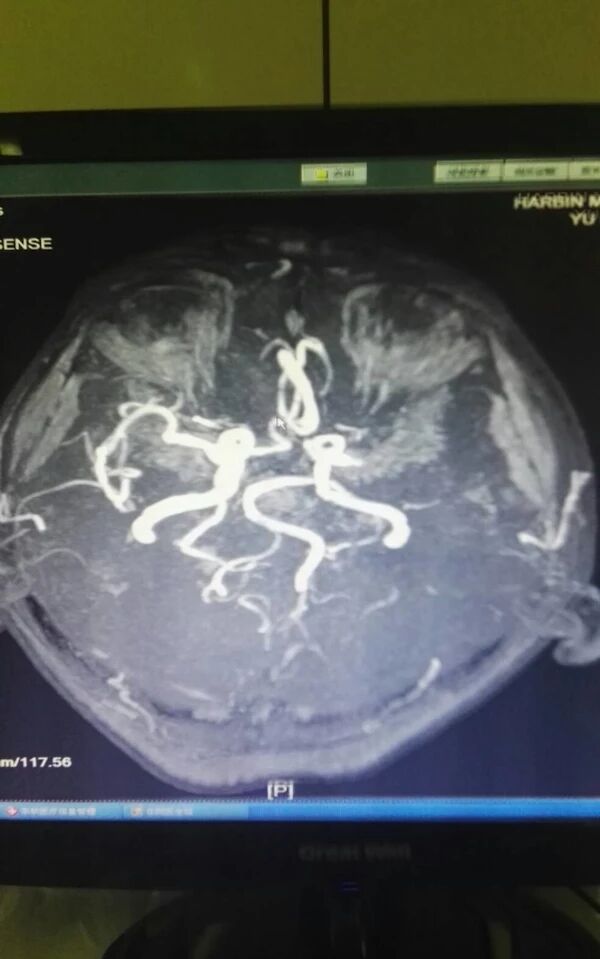

完善相关检查后,急诊行全脑血管造影术

示右侧大脑后动脉P1段不显影,右侧后交通动脉开放。左侧P1中段闭塞,左侧前循环无明显代偿。考虑该血管为责任血管,急诊行血管开通术。